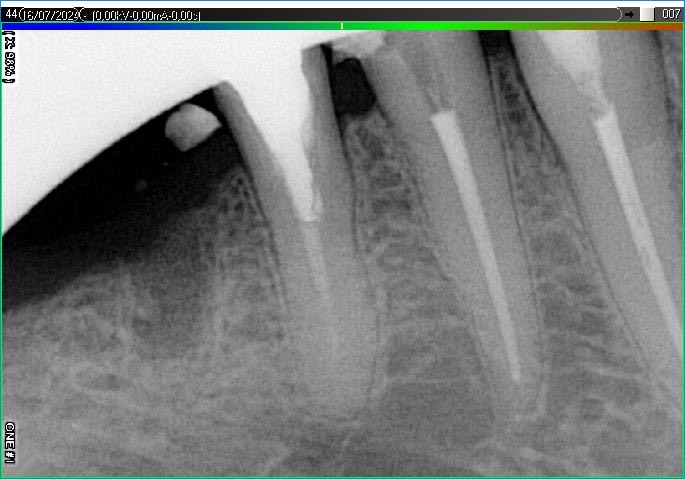

Вилучення інструменту з каналів зуба